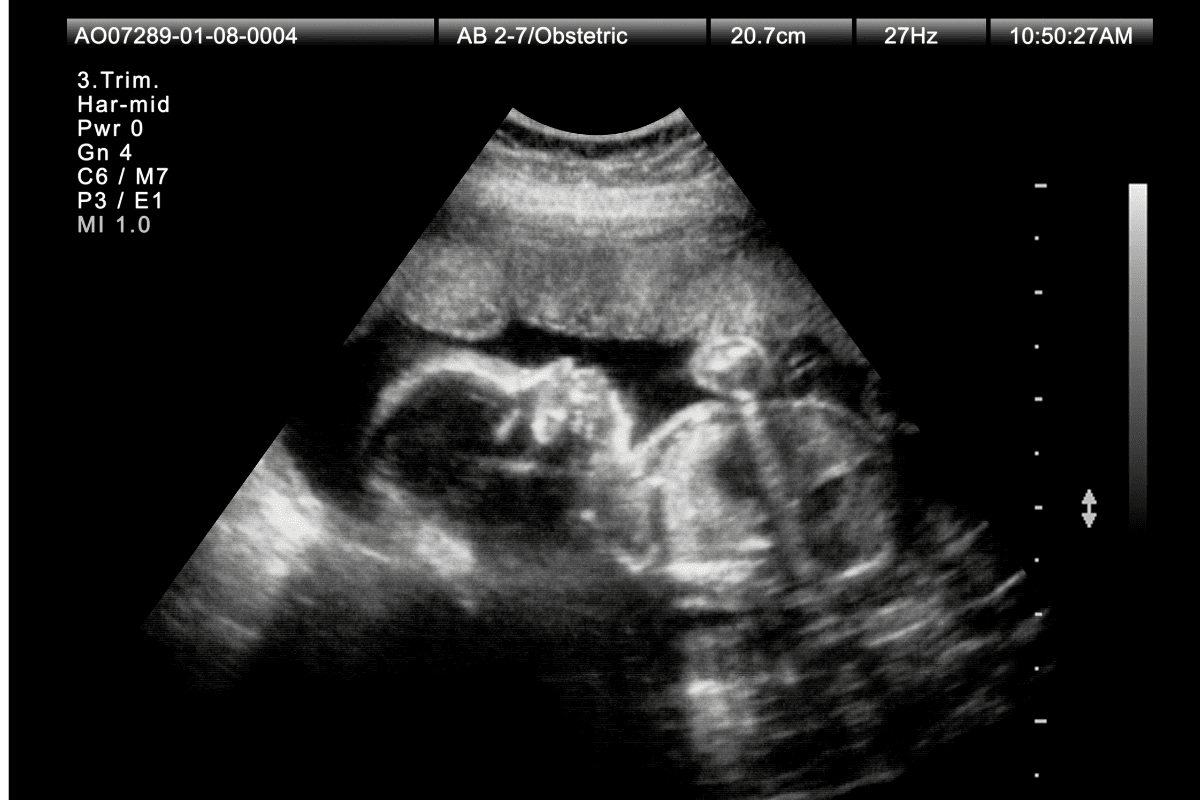

Пренатальный скрининг третьего триместра — это важный этап наблюдения за развитием плода, который проводится на сроке 30–34 недели беременности. Его цель — оценить общее состояние ребенка, выявить возможные отклонения в развитии на поздних сроках, а также определить риски осложнений, таких как задержка внутриутробного развития, гипоксия или патологические изменения в плаценте. УЗИ в третьем триместре беременности помогает врачам своевременно принять необходимые меры, чтобы обеспечить безопасность будущей мамы и малыша в оставшиеся недели беременности и во время родов.

Во время УЗИ в третьем триместре врачи оценивают биометрические показатели плода – массу тела, окружность головы и живота, длину бедренной кости. Это помогает определить соответствие размеров плода гестационному сроку и исключить задержку внутриутробного роста. Дополнительно проверяется работа сердца и других внутренних органов плода, положение в матке, зрелость плаценты, объем околоплодных вод и состояние пуповины.

Скрининг третьего триместра включает несколько диагностических процедур, которые позволяют получить полную картину состояния плода и подготовки организма женщины к родам. Основным методом является УЗИ в третьем триместре беременности, которое проводится через переднюю брюшную стенку.

Во время УЗИ врач измеряет параметры плода: вес, окружности головы и живота, длину костей, оценивает работу сердца, развитие внутренних органов, положение малыша в матке и состояние плаценты. Дополнительно может быть выполнена допплерометрия — оценка кровотока в сосудах плода, пуповины и матки, а также кардиотокография (КТГ) — исследование сердцебиения ребенка и активности матки.